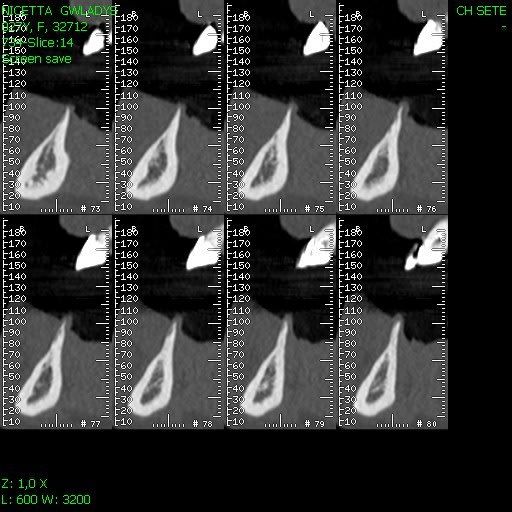

la patiente a 27 ans, elle aperdu ces 4 incisives mandibulaires il ya plusieurs années dans un accident.

La crête osseuse est ultra résorbée et très fine.

mon idée c'est que c'est possible, et vous vous le feriez? et quelle prothèse?